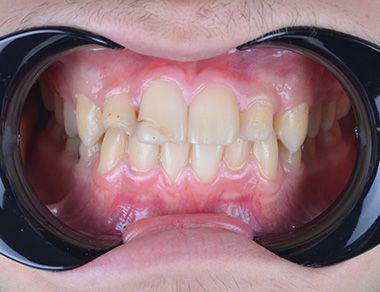

Glenn T. broke 2 teeth as a result of an accident in his childhood. These teeth were filled and the fillings were aged. Glenn was unhappy because of the gaps between his teeth. He also did not like the angle of his front two teeth. He wanted to have his teeth done before he started university. He decided to have invisalign in Turkey with his family.

Firstly, we treated the gap between the teeth with Invisalign. We also corrected the angle of the front teeth. Invisalign Lite was enough. Glenn visited Turkey 4 times in a period of 8 months. During his last visit, we replaced the old fillings in his front teeth with composite bonding. We performed lingual retrainer to maintain the alignment of the teeth. We produced an sx plate for him to use at night and delivered it to him. Glenn was very happy. He said he wanted to study at a dentistry faculty.